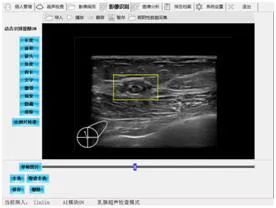

视尚医疗开发的系统和设备为乳腺癌筛查医师赋能,特别是降低基层筛查人员使用超声设备和阅读超声图像的门槛,提升基层乳腺癌超声检查和初诊的整体水平,提高筛查效率,减少漏筛及漏诊,从而有助于解决我国乳腺癌筛查超声医师严重短缺和基层筛查水平严重不均的问题,实现乳腺癌筛查基层化、标准化和规模化。2021年,视尚医疗的SSUN110便携式智能超声设备作为上海市第七批医疗援藏队指定专用设备,已经为西藏日喀则地区当地妇女进行了数千例的乳腺癌超声筛查。

便携式智能彩色超声诊断仪乳腺超声影像智能辅助诊断系统